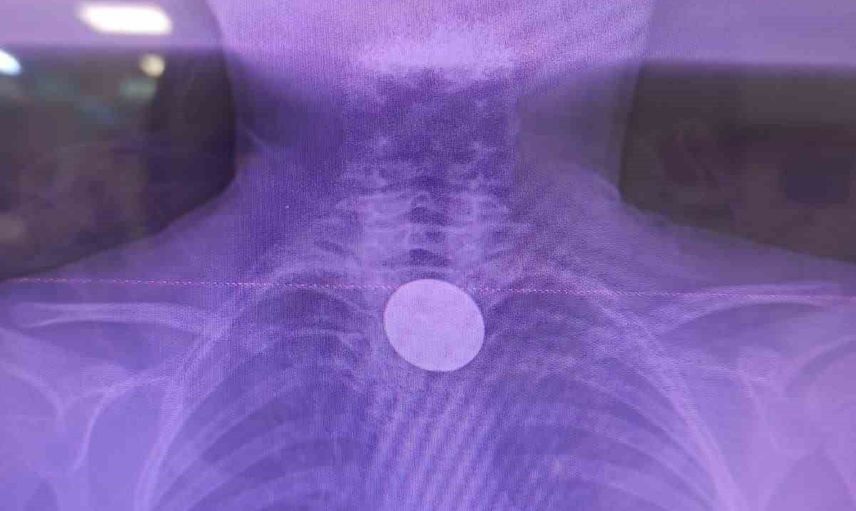

Siirt'te 8 yaşındaki Y.K., boğazına değeri 5 lira olan bir madeni para kaçması sonucu hastaneye başvurdu. Siirt Eğitim ve Araştırma Hastanesi'nde yaşanan bu olay, doktorların hızlı müdahalesi sayesinde başarılı bir şekilde sonuçlandı.

Ailesi tarafından hastaneye getirilen çocuk, yabancı cisim yutma şikayeti ile acil servise alındı. Yapılan detaylı incelemeler sonucunda, madeni paranın yemek borusuna kadar ilerlediği belirlendi. Uzman ekip, gastroenteroloji doktoru Dr. Yaren Dirik ve kulak burun boğaz hekimi Yasin Gökçınar tarafından gerçekleştirilen operasyonla para çıkarıldı.

Siirt Eğitim ve Araştırma Hastanesi Başhekim Yardımcısı Uzman Dr. Burak Özkan, çocuklarda yabancı cisim yutma vakalarının ciddi riskler taşıdığını vurgulayarak, "Hastanemize başvuran 8 yaşındaki hastamızın yemek borusuna kaçan madeni para, ekiplerimizin koordineli çalışması ile sorunsuz bir şekilde çıkarılmıştır. Tedavi süreci iyi geçti ve hastamız taburcu edilmiştir" şeklinde konuştu.